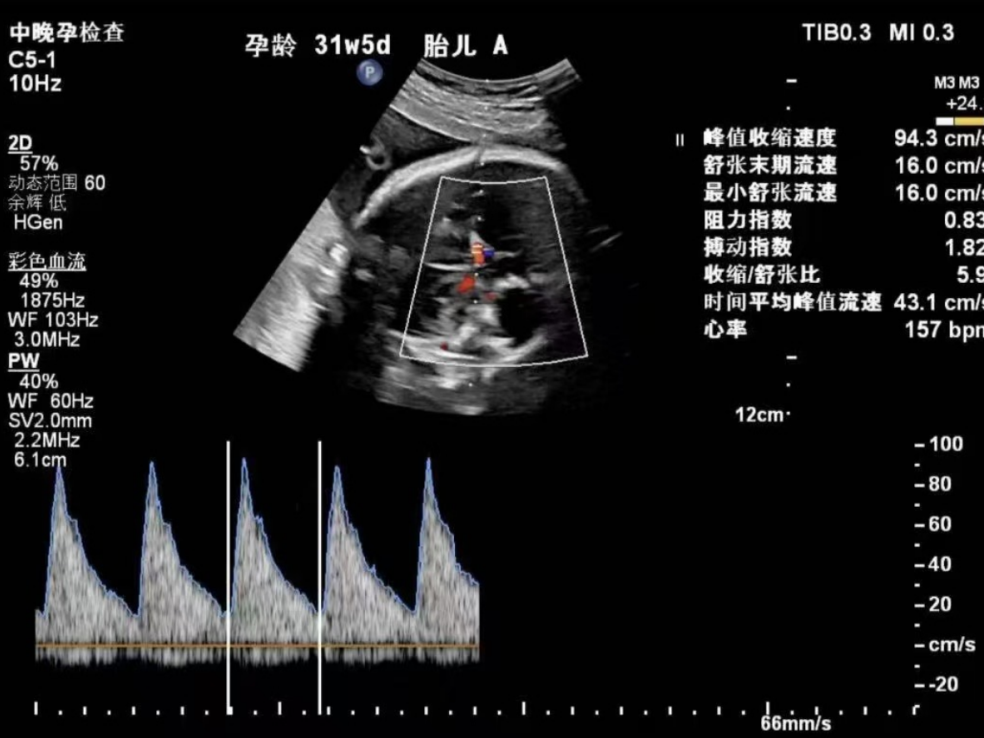

多年来,贵州航天医院各科室紧跟医学前沿,不断强技术、补短板,大力开展新技术、新项目,完成了许多高精尖、高难度、本地区“首例”的技术,填补了医院医疗技术空白,满足了群众日益增长的医疗需求。 复杂性双胎超声监护耗时耗力,技术难度大,风险高,为填补本地区复杂性双胎的超声监护技术空白,我院超声科在遵义市率先开展了此项技术,有效满足了双胎孕妇产检需求,保障了双胎新生儿的平安健康。 本期,我们将为大家带来超声科特色技术——复杂性双胎的超声监护。 案例分享 案例一 28岁的孕妇,自然受孕,怀有单绒毛膜双羊膜囊双胎(MCDA),在我院定期产检的过程中,孕32周超声检查发现两个胎儿的大脑中动脉血流流速(MCA-PSV)相差>0.7倍数的正常值(MoM),高度怀疑发生了双胎贫血红细胞增多序列征(TAPS)。为进一步明确诊断,产科立即组织超声科、手术室、新生儿科等科室进行多学科会诊(MDT),诊断为:双胎贫血红细胞增多序列征(TAPS),在征得孕妇及其家属的同意后,决定提前分娩,及时保障了两名胎儿的生命和健康。 双胎大脑中动脉血流 双胎贫血红细胞增多序列征(TAPS) 案例二 一名26岁的孕妇,是完全双角子宫,且为左侧子宫妊娠,怀有单绒毛膜双羊膜囊双胎(MCDA),一直在我院规律产检,孕16周时,超声检查发现双胎生长不一致,体重相差超过25%,考虑子宫畸形合并早发选择性胎儿宫内生长受限。孕妇在咨询相关上级医院专家后,得到减胎的建议,又前来我院咨询,在我院超声科和产科的合作下,查阅了大量文献、认真评估检查报告后,建议孕妇继续双胎妊娠。在规律、严密的超声监护下,双胎除体重差异外未出现严重胎儿并发症,在34周进行了分娩,截至目前,新生儿生长发育均正常。 胎儿生长曲线及子宫畸形三维重建 出生时体重差异 十月龄时 案例三 一名30岁的孕妇,自然受孕,怀有单绒毛膜双羊膜囊双胎(MCDA),在孕22周时超声检查发现双胎发生了选择性胎儿宫内生长受限,遂转诊到上级医院拟行胎儿镜治疗,但在行治疗的前一天,较小的胎儿在宫内发生死亡,在充分与孕妇及家属沟通后,要求继续妊娠,在定期规范的产检下,严密监测胎儿生长发育及胎儿颅脑MRI影像,最终在孕37周时通过剖宫产分娩,目前新生儿生长发育情况良好。 双胎之一胎死宫内(右图) 贵州航天医院自2021年开展复杂性双胎的超声监护以来,已服务大量双胎孕妇,集齐了所有单绒毛膜双羊膜囊双胎(MCDA)并发症病例,由经验丰富的超声医师进行此项检查,产科专业团队进行双胎的规范化监护和分娩,并与重庆医科大学附属第一医院建立了转诊通道,能够及时获得该院专家的指导和支持,为广大孕产妇提供优质、全面的医疗保障。 点击跳转贵州航天医院便民服务电话 什么是复杂性双胎的超声监护 “双胎”被称为产科之王,单绒毛膜双胎则为王中王,主要是因为单绒毛膜双羊膜囊双胎(MCDA)两胎儿共用一个胎盘,胎盘中存在血管吻合。 双胎妊娠的产前筛查及诊断主要依靠超声,相对于单胎妊娠,双胎妊娠并不是单胎检查的重复,双胎妊娠尤其是复杂性双胎的超声诊断更为重要的是关注双胎间循环的关联,双胎间生理及病理改变的相互影响,双胎间血流动力学监测及双胎间差异比较。 超声如何诊断 复杂性双胎并发症 在孕14周以前,超声要明确双胎的绒毛膜性:是单绒毛膜(MC)还是双绒毛膜(DC);孕10周前,可以通过孕囊的个数确定绒毛膜性;孕11周—14周,可以通过胎儿的性别、双胎之间隔膜的厚度、双胎儿分隔膜处胎盘的形态等来区分绒毛膜性。 双绒毛膜双胎的管理和单胎差不多,基本不需要增加超声检查的频次。单绒毛膜的管理相对谨慎,按照国际国内指南规范,单绒毛膜双胎自第16周起,每两周对双胎儿进行生长发育评估及血流检查。 复杂性双胎的超声监护,对超声医生技术要求较高,孕早期需对双胎的绒毛膜性进行精确判断;产科医生根据绒毛膜性制定孕期的产检计划;超声医生掌握胎儿宫内情况,及时与产科医生沟通,精确了解胎儿宫内安危后制定合适的治疗方案,给出适当的终止妊娠时机;复杂性双胎一般都面临早产的风险,所以新生儿团队的专业保障不可或缺,降低新生儿出生后的并发症及提高新生儿生活质量。复杂性双胎的较好妊娠结局,是通过孕期超声科、产科紧密合作,及新生儿出生后新生儿科管理多学科团队合作所获得的。 贵州航天医院超声科专家团队 吴艳辉 超声科 学科带头人 主任医师 专业擅长:从事超声诊断工作约30年,对心血管、小器官超声、超声引导下介入等具有丰富的临床经验。 骆科美 超声科 副主任医师 专业擅长:从事超声诊断工作33年,对胎儿心脏及颅脑、妇产超声诊断、盆底超声等诊断具有丰富的临床经验。 胡大海 超声科 副主任医师 专业擅长:从事超声工作17年,对心血管、外周血管、浅表器官超声诊断等具有丰富的临床经验。 刘 敏 超声科 副主任医师 专业擅长:从事超声诊断工作20余年,对妇产科超声、心脏血管超声诊断具有丰富的临床经验。 贵州航天医院超声科简介 贵州航天医院超声科配备多种超声检查设备(飞利浦彩超(IU-22、IU-Elite、HD11、Q5、Q7),迈瑞超声I9、DC-6、DC-8、GE-E8及床旁机,彩色超声诊断仪等),设有心血管诊室、妇产科诊室、腹部诊室、绿色通道、浅表小器官等检查室。 • ✦ 专科特色 ✦ • 四肢血管超声检查、双胎产前筛查及超声监护、超声造影检查技术、介入超声临床应用、经颅脑实质超声辅助筛查诊断帕金森病、女性性早熟超声诊断、盆底超声检查等。 NT超声检查 超声介入引导 肝脏超声造影 甲状腺造影 颅脑超声帕金森辅助检查 乳腺超声造影 上肢动静脉造瘘超声检查 双胎超声筛查 下肢血管超声检查 右心造影 • ✦ 诊疗范围 ✦ • 科室业务覆盖腹部、泌尿、妇科、产科(常规、NT筛查、III级筛查超声检查及高危妊娠监护)、成人心脏、外周血管、浅表器官(包含甲状腺、乳腺、阴囊、眼睛等)、颅脑(小儿颅脑、成人颅脑)、小儿肺超、造影、盆底、腹直肌、肌骨神经等检查及各种介入引导。